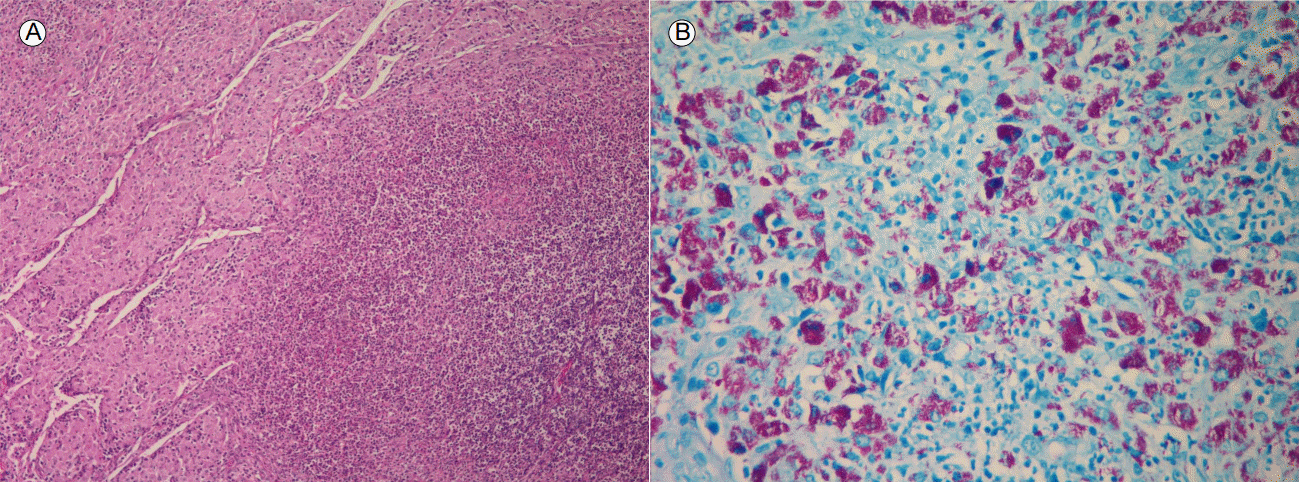

Figure 1.

(A) Hematoxylin and eosin staining (×100) of a laparoscopic excision of the paraaortic lymph node. Shown is the dense neutrophilic aggregation. (B) Ziehl-Neelsen staining (×400) of acid fast bacilli within macrophages of the patient’s paraaortic lymph node.